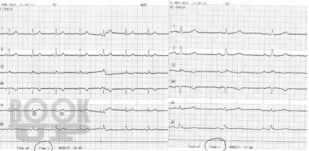

Наглядная ЭКГ

Стаценко И. Ю. Наглядная ЭКГ : учебное пособие / И. Ю. Стаценко, В. С. Сергеев, М. Е. Стаценко. - М. : Логосфера, 2022. - 82 c. - ISBN 9785986570907. - Текст : электронный // ЭБС "Букап" : [сайт]. - URL : https://www.books-up.ru/en/book/naglyadnaya-ekg-15736724/ (дата обращения: 27.04.2026). - Режим доступа : по подписке.

Учебное пособие по электрокардиографии для студентов-медиков, осваивающих пропедевтику внутренних болезней. Книга учит анализировать ЭКГ, выявлять ключевые патологии: гипертрофии сердца, ишемическую болезнь сердца, аритмии, инфаркт миокарда. Через структурированный материал и тестовые задания формирует профессиональные компетенции:

• ПК-1 (анализ и синтез медицинских данных),

• ПК-5 (диагностика патологий по ЭКГ),

• ПК-6 (классификация симптомов по международным стандартам).

Расшифровка ЭКГ - это базовый навык врача, владение которым ведет к уверенной клинической практике.